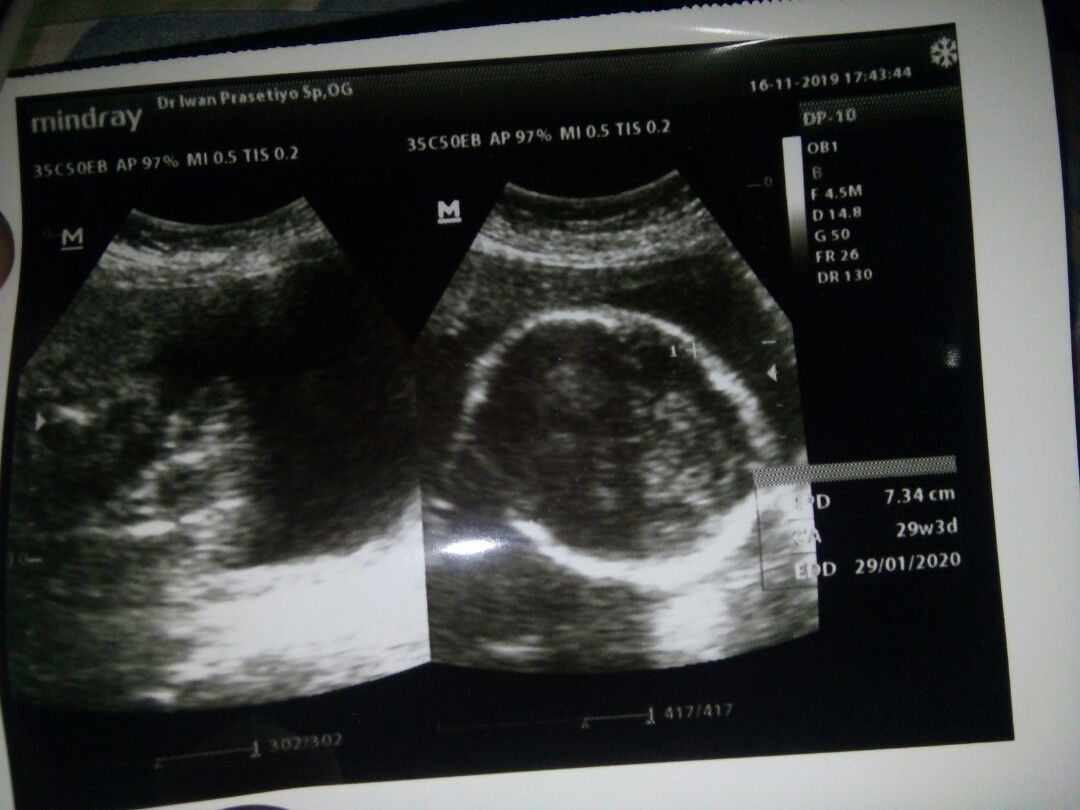

Bun hari ini aku usg ... Di usia kndungan mnurut bidan 27w6d tp mnurut dokter kok 29w3d kok bda seminggu ya ?? trus kata dokter masih sungsang ... Ada yg kya aku gk bun ? semoga lancar smpai di hari persalinan nanti ya bun mohon doa'y ??? karna tkut di kehamilan k 2 ini hrus sc lgi ???